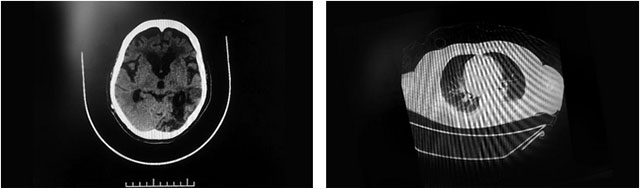

▲ 患者多發(fā)性腦梗,且肺部感染嚴(yán)重

7月23日,顧女士再次突發(fā)腦梗,這次就沒(méi)那么幸運(yùn),其左頸內(nèi)動(dòng)脈、大腦中動(dòng)脈嚴(yán)重閉塞,高達(dá)75%以上,隨后在救治醫(yī)院進(jìn)行了腦血管造影+左頸動(dòng)脈CTO病變血管成形術(shù)。不久,顧女士病情再次加重,其頭部CT提示:腦室擴(kuò)張,又于8月14日全麻下行腦室—腹腔分流術(shù);之后又因肺部感染較重,咳痰較多、呼吸困難,于8月18日行氣管切開(kāi)呼吸機(jī)輔助呼吸。